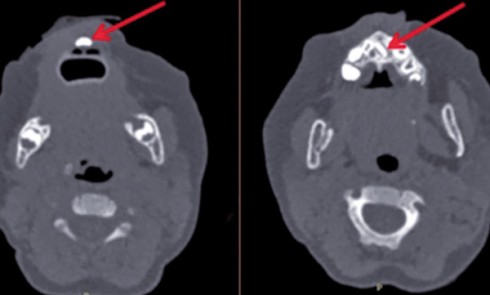

Article réservé à nos abonnés À propos d’une lésion labiale

1. Quel diagnostic évoquez-vous ?a. Un lymphomeb. Un kyste salivairec. Un carcinome épidermoïded. Aucun de ces diagnostics 2. Quelle attitude préconisez-vous ?a....